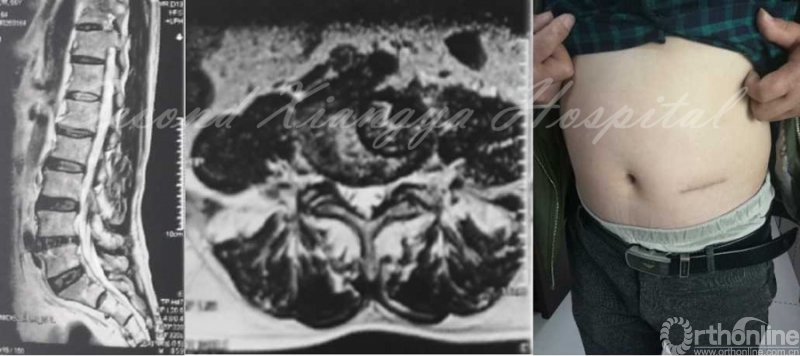

MRI:L4/5椎间盘右侧突出,非游离,无钙化,伴侧隐窝狭窄。

MRI-T2、MRI-T1

MRI-TRANSVERSE